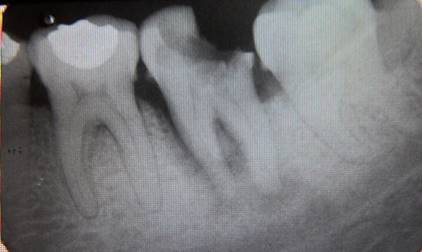

A 40-year-old female patient who attends the endodontics clinic after being referred by her health center to assess and treat tooth 37, which presents a deep carious lesion. Her dental history was taken, and an oral exam was performed. Pulpal sensitivity tests, performed with tetrafluoroethane (Endo-Ice, Coltene Whaledent, USA 2010), as well as periapical sensitivity tests, were negative. A 5-mm gingival sulcus was found on probing in the mesial area, as well as an absence of tooth mobility and surrounding soft tissue without inflammation. The radiographic study (Fig. 1) showed crown destruction on the occlusal and distal sides, pulp chamber communicating with the oral cavity, radiolucent lesion associated with apex of the distal root, and peripheral radiolucent lesion in mesial root including furcation area. The data were collected and analyzed, leading to the diagnosis of pulp necrosis with asymptomatic apical periodontitis.

Periapical lesion affecting both roots and furcation area involvement